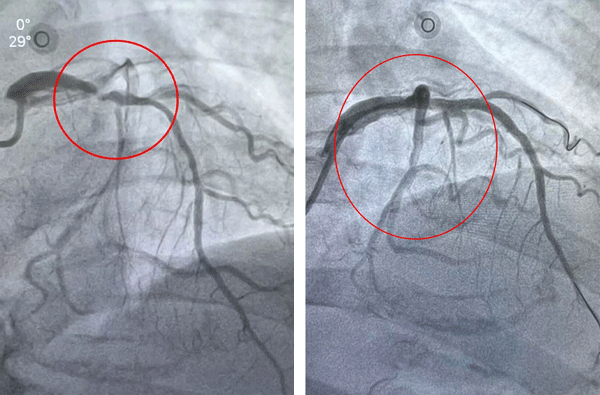

▲术前 ▲术后

另一例患者郝先生发病超24小时就诊,冠脉造影显示冠脉多发重度狭窄,右冠脉远段狭窄达95%,且血管走形迂曲、合并严重钙化,介入治疗难度极高。面对挑战,介入团队凭借熟练的技术与密切配合,历经两小时精准操作,成功完成右冠脉血运重建。